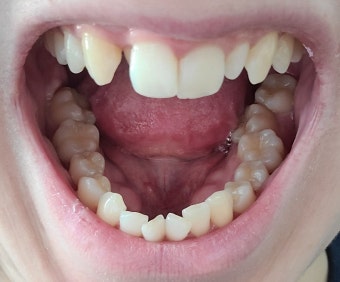

- 임플란트는 일반 치아보다 음식물이 끼기 쉬움 → 치실·워터픽 등 적극 활용.

- 개인에게 맞는 구강 용품 추천 및 사용법 교육 가능.

- 틀니 적응 중 불편함은 즉시 치과 방문 → 지속 착용은 잇몸에 무리.

- 틀니 착용자는 의치성 구내염 주의 → 잇몸 염증 증상 시 검진 필요.

- 증상 방치 시 조직 검사 또는 외과적 치료가 필요할 수 있음.